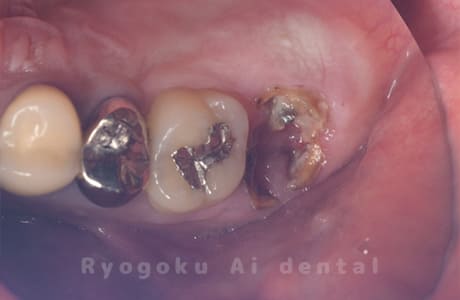

Case27

-

重度カリエス

歯牙移植咬合面術前 -

移植する親知らず

歯牙移植術直後咬合面

歯牙移植術後咬合面

歯牙移植術前側面

歯牙移植術中側面

歯牙移植術後側面

- 原因

- 重度カリエス

- 治療内容

- 自家歯牙移植、部分矯正

- 治療費用

- 220,000円(移植費用)

110,000円(部分矯正費用)

虫歯が大きく、保存不可能となった歯を上の親知らずと交換する自家歯牙移植を行いました。移植歯が小ぶりであったため、部分矯正を行い問題なく噛み合い、経過良好です。